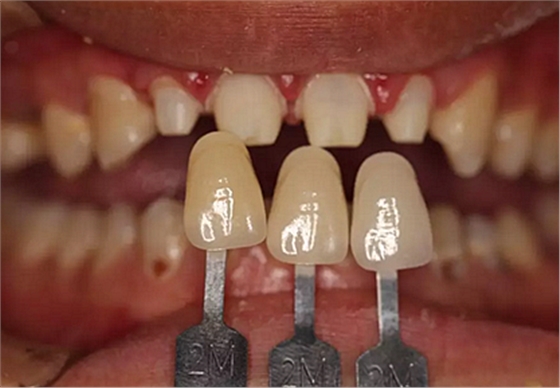

兩周后,主人帶我們往醫(yī)院拆線,取模,比色,為我們重新量身定制了一套堅(jiān)固的“外套”。